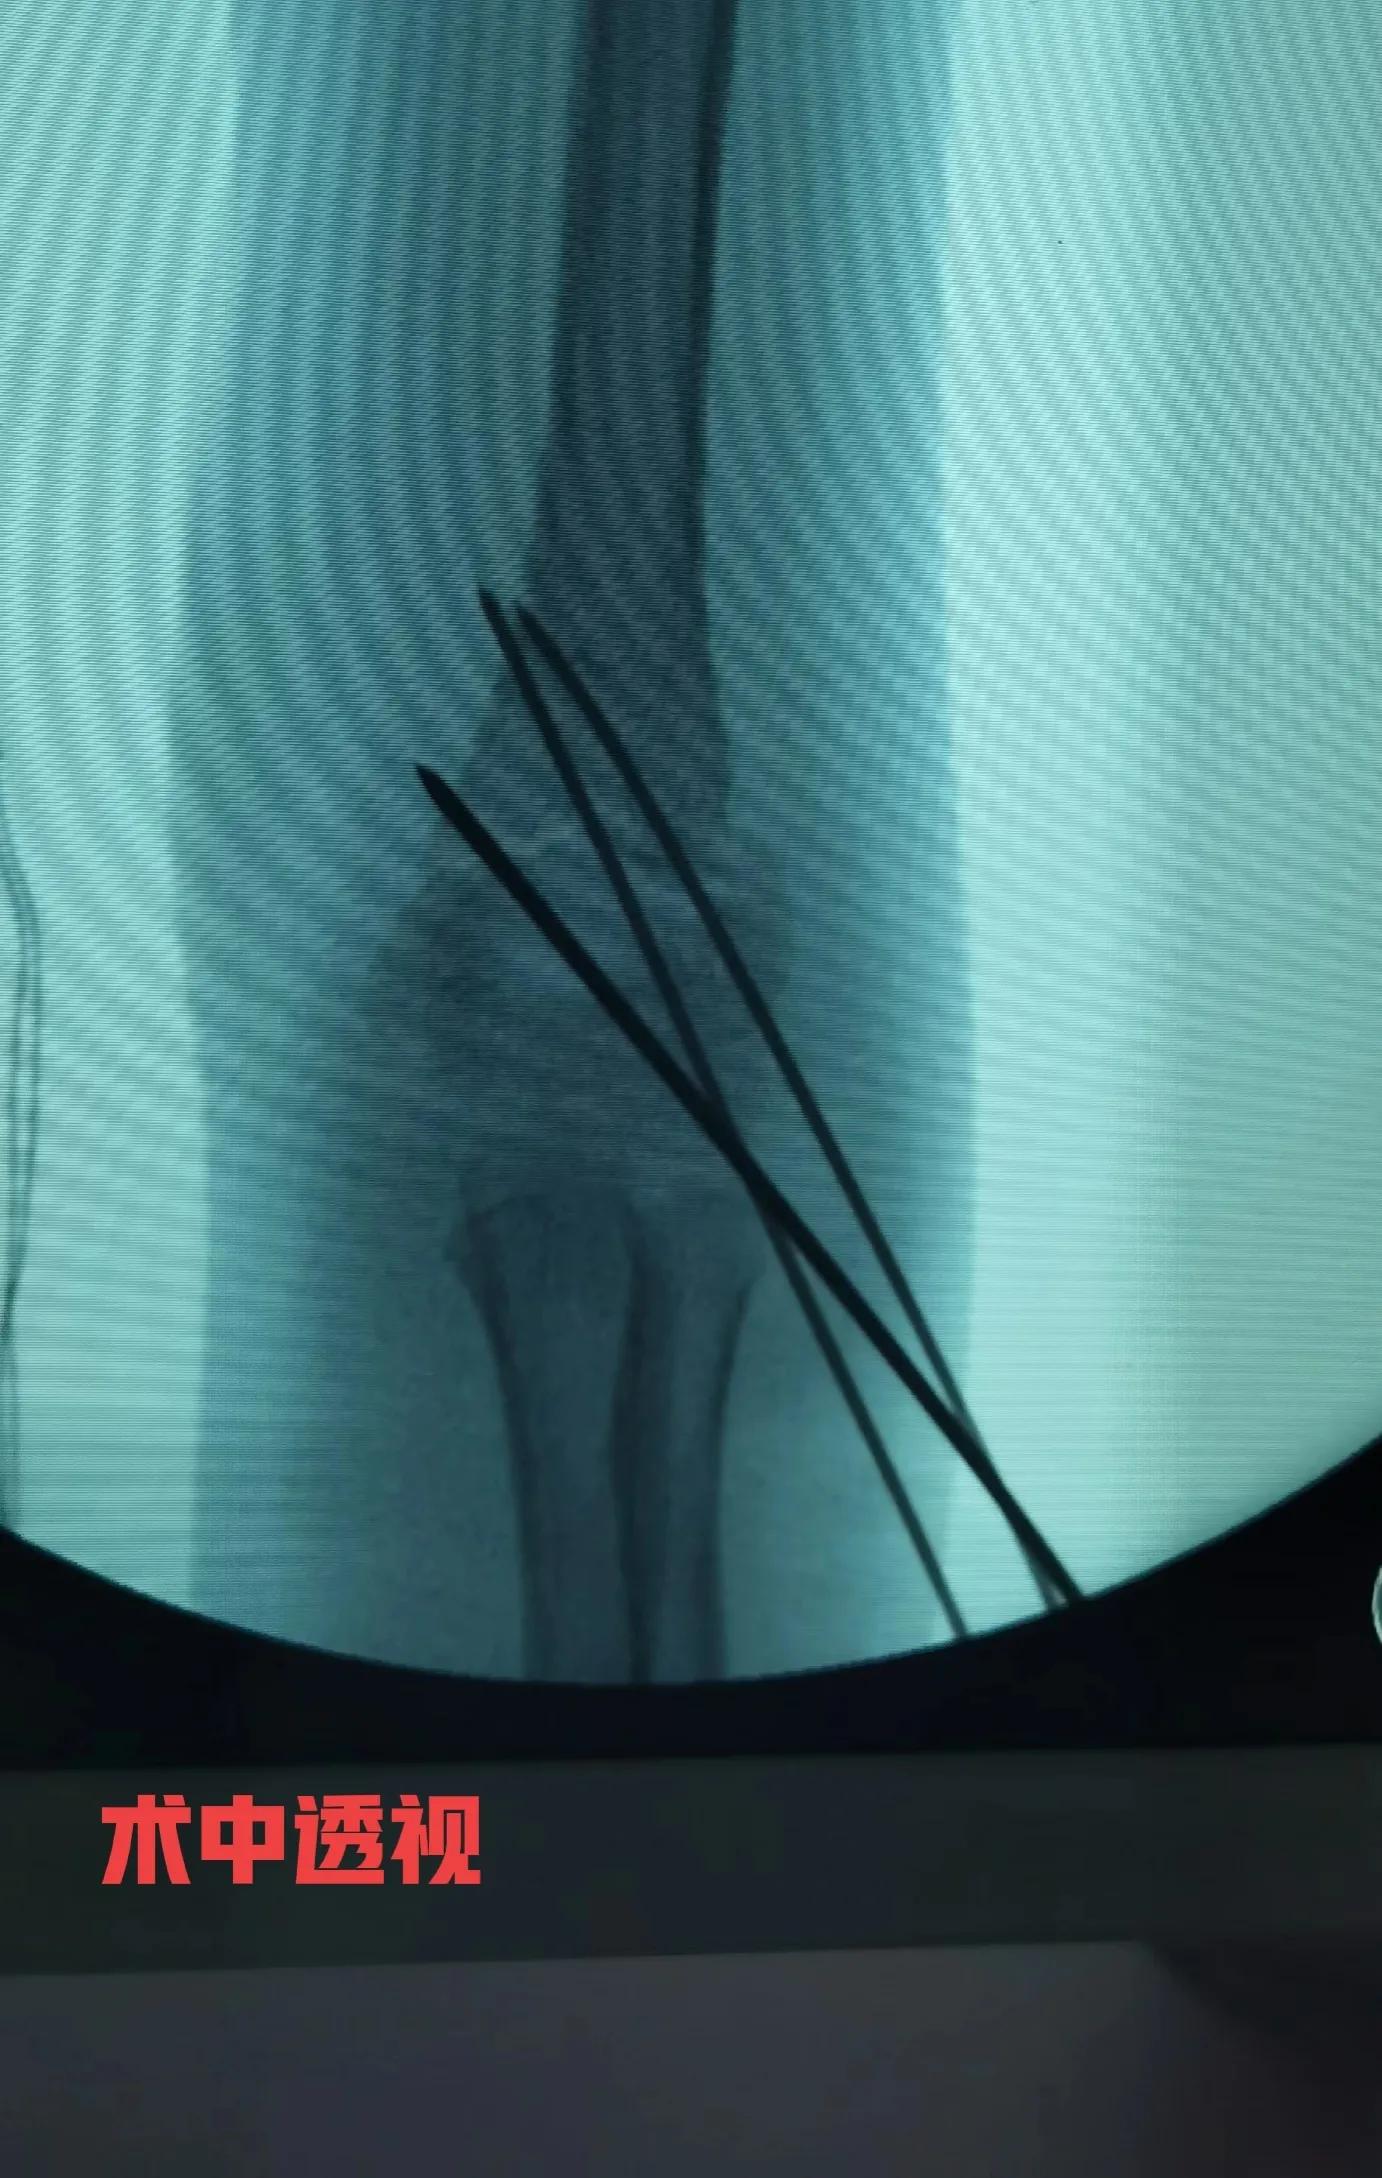

肱骨髁上骨折一般是指肱骨内、外髁上2cm范围内的骨折,在小儿骨折中非常常见的一种骨折,多见于3到12岁的小孩,在小儿肘关节骨折中占比达到80%以上。该骨折可合并血管,神经的损伤,处理不当可引起缺血性肌挛缩,骨化肌炎,肘关节内外翻畸形等。针对非移位骨折或者不完全性骨折单纯石膏托外固定就可以。针对有明显移位的骨折,以前通常都是通过闭合手法复位加石膏托外固定,由于骨折端难以复位,或者骨折端的不稳定性,患肢消肿,石膏托松紧度改变,容易导致骨折复位丢失,甚至骨折复位失效,骨折再次移位,再次复位效果欠佳,反复调节增加小儿痛苦等。目前逐渐倾向于手术治疗,主要采用手法闭合复位克氏针内固定,辅助石膏托外固定,是一种零切开的微创手术,患儿家长容易接受的一种术式。没有特殊情况,基本上手术当天或者术后第一天就可以出院。

病例 女性,7岁,跌伤,右肱骨髁上骨折